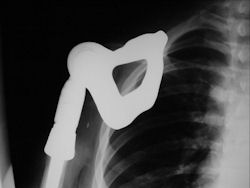

Gross Pathology: Osteosarcoma of Proximal Humerus

- originates from metaphysis of the proximal humerus, extends into surrounding soft tissues

- large soft tissue component that is crossing the glenohumeral joint

- was removed via an extra-articular resection, including scapula (Tikhoff-Linberg resection)

Examples of radical limb sparing surgeries for osteosarcomas in various anatomic locations (distal femur, proximal tibia, proximal humerus, scapula)

In each case, the tumor and bone from which it arose were resected. This required meticulous dissection, mobilization and preservation of adjacent pertinent neurovascular structures. In each case presented here, the defect was reconstructed with a special modular segmental tumor prosthesis. This also replaces the adjacent joint in many instances.

Proximal Humerus: Radical Limb Sparing Extra-Articular Resection and Prosethetic Reconstruction